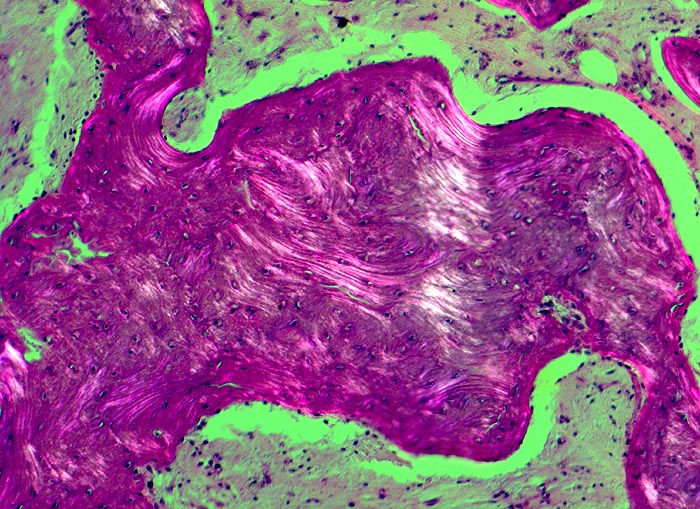

• Prominente Zementlinien sind mosaikartig angeordnet.

An den betroffenen Stellen ist sowohl der Knochenabbau als auch der Knochenanbau gesteigert. Die Osteoklasten sind auffallend gross und enthalten sehr viele Kerne (> 3518). Die aktivierten Osteoblasten produzieren verdickte und grob geflochtene Spongiosabälkchen. Der neugebildete Knochen ist strukturell und morphologisch abnorm und schlecht mineralisiert. Der Knochen wird dadurch weich und anfällig auf Frakturen oder Deformation unter Belastung (nach vorne gebogene Säbelscheidentibia). Das Knochenmark wird ersetzt durch fibrovaskuläres lockeres Stroma, welches an Granulationsgewebe erinnert. Mikroskopisch werden eine osteolytische Initialphase, eine Umbauphase mit verstärkter Knochenneubildung und eine sklerosierende Stabilisationsphase mit strukturellem Umbau und Spongiosierung der Kortikalis (verbreiterte spongiosaartige Kortikalis) unterschieden.